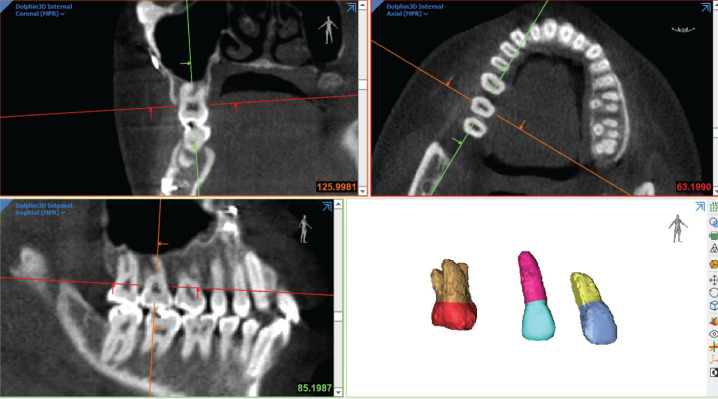

Methods: Eighteen subjects, aged 18 to 65 years with pre-surgery (T0), post-surgery (T1), and long-term follow-up (T2) CBCT records were included. Sixteen control subjects, aged 17.67 to 62.33 years, with pre-treatment (T0), progress (T1), and long-term progress orthodontic (T2) CBCT records were also used. Maxillary central incisor, canine, and first molar roots were segmented. The volume, surface area, and root length changes were analyzed using repeated measures ANOVA and mean differences across follow-up periods. Significance was set at p<0.05.

Abstract Image